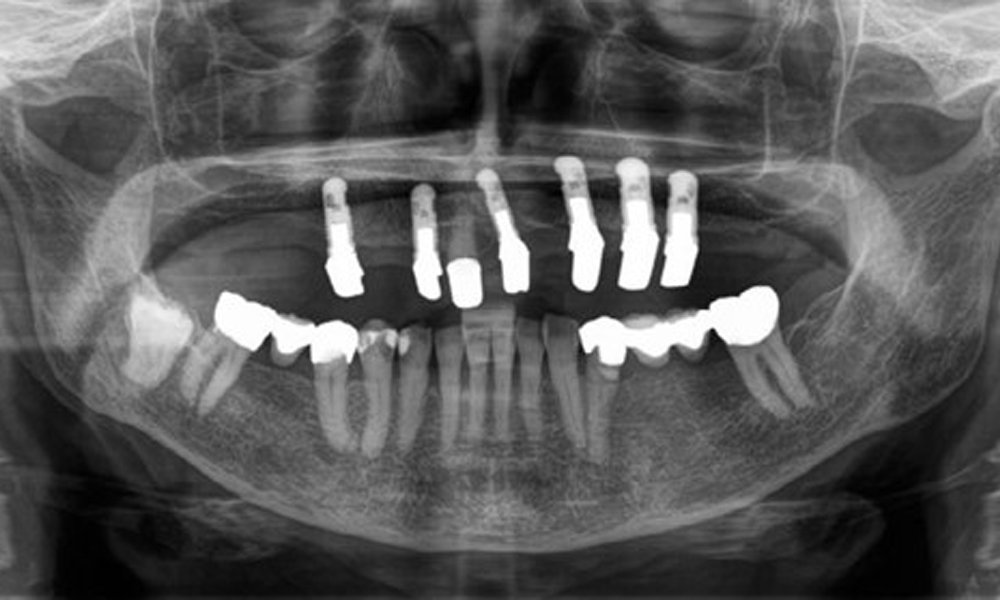

The patient was fitted with a combined removable maxillary telescopic prosthesis more than 25 years ago (Fig. 1, Fig. 2, Fig. 3) and is very happy with her dentures. The patient has an adequate fixed denture for the mandible (Fig. 4).

The dental findings are as follows: Combined removable implant and tooth-supported telescopic prostheses on implants 15, 13, 21, 23, 24, 25 and tooth 11 (Fig. 1, Fig. 2, Fig. 3). The patient was fitted with a fixed mandibular denture. Adequate bridges were present over 37 to 34 and 45 to 47 (Fig. 4), the crown margins were intact and there were no active caries. A composite filling with a marginal gap was present on tooth 43. There was mandibular gingival recession, exposing 1 to 3 mm of root surface. This also applies to 11.

The radiological findings show partially edentulous dentition with maxillary implants for teeth 15, 13, 21, 23, 24, 25 and a telescopic crown on tooth 11. Adequate mandibular bridges spanning 37 to 34 and 45 to 47 are present. 48 is impacted. There are suspected secondary caries distally on 43 and mesially on 44. 44 is restored with a non-radiopaque cavity lining. There is generalised horizontal bone loss of approx. 10% to 30% and localised vertical bone loss affecting teeth 22 and 42 (Fig. 5).